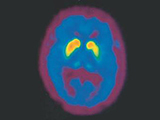

Parkinson ist die zweithäufigste neurodegenerative Erkrankung des Gehirns. Weltweit sind schätzungsweise 7-10 Millionen Menschen davon betroffen, doch die Zahl wird aufgrund des Alterns der Bevölkerung in den nächsten Jahren deutlich zunehmen. Bei der Mehrzahl der Patienten wird die Krankheit um das 60. Lebensjahr festgestellt. Allerdings kann die Krankheit, vor allem bei erblichen Formen, auch schon viel früher ausbrechen: etwas jeder zehnte Patient erkrankt vor dem 40. Lebensjahr. Generell sind Männer etwas häufiger von der Parkinson-Krankheit betroffen als Frauen.